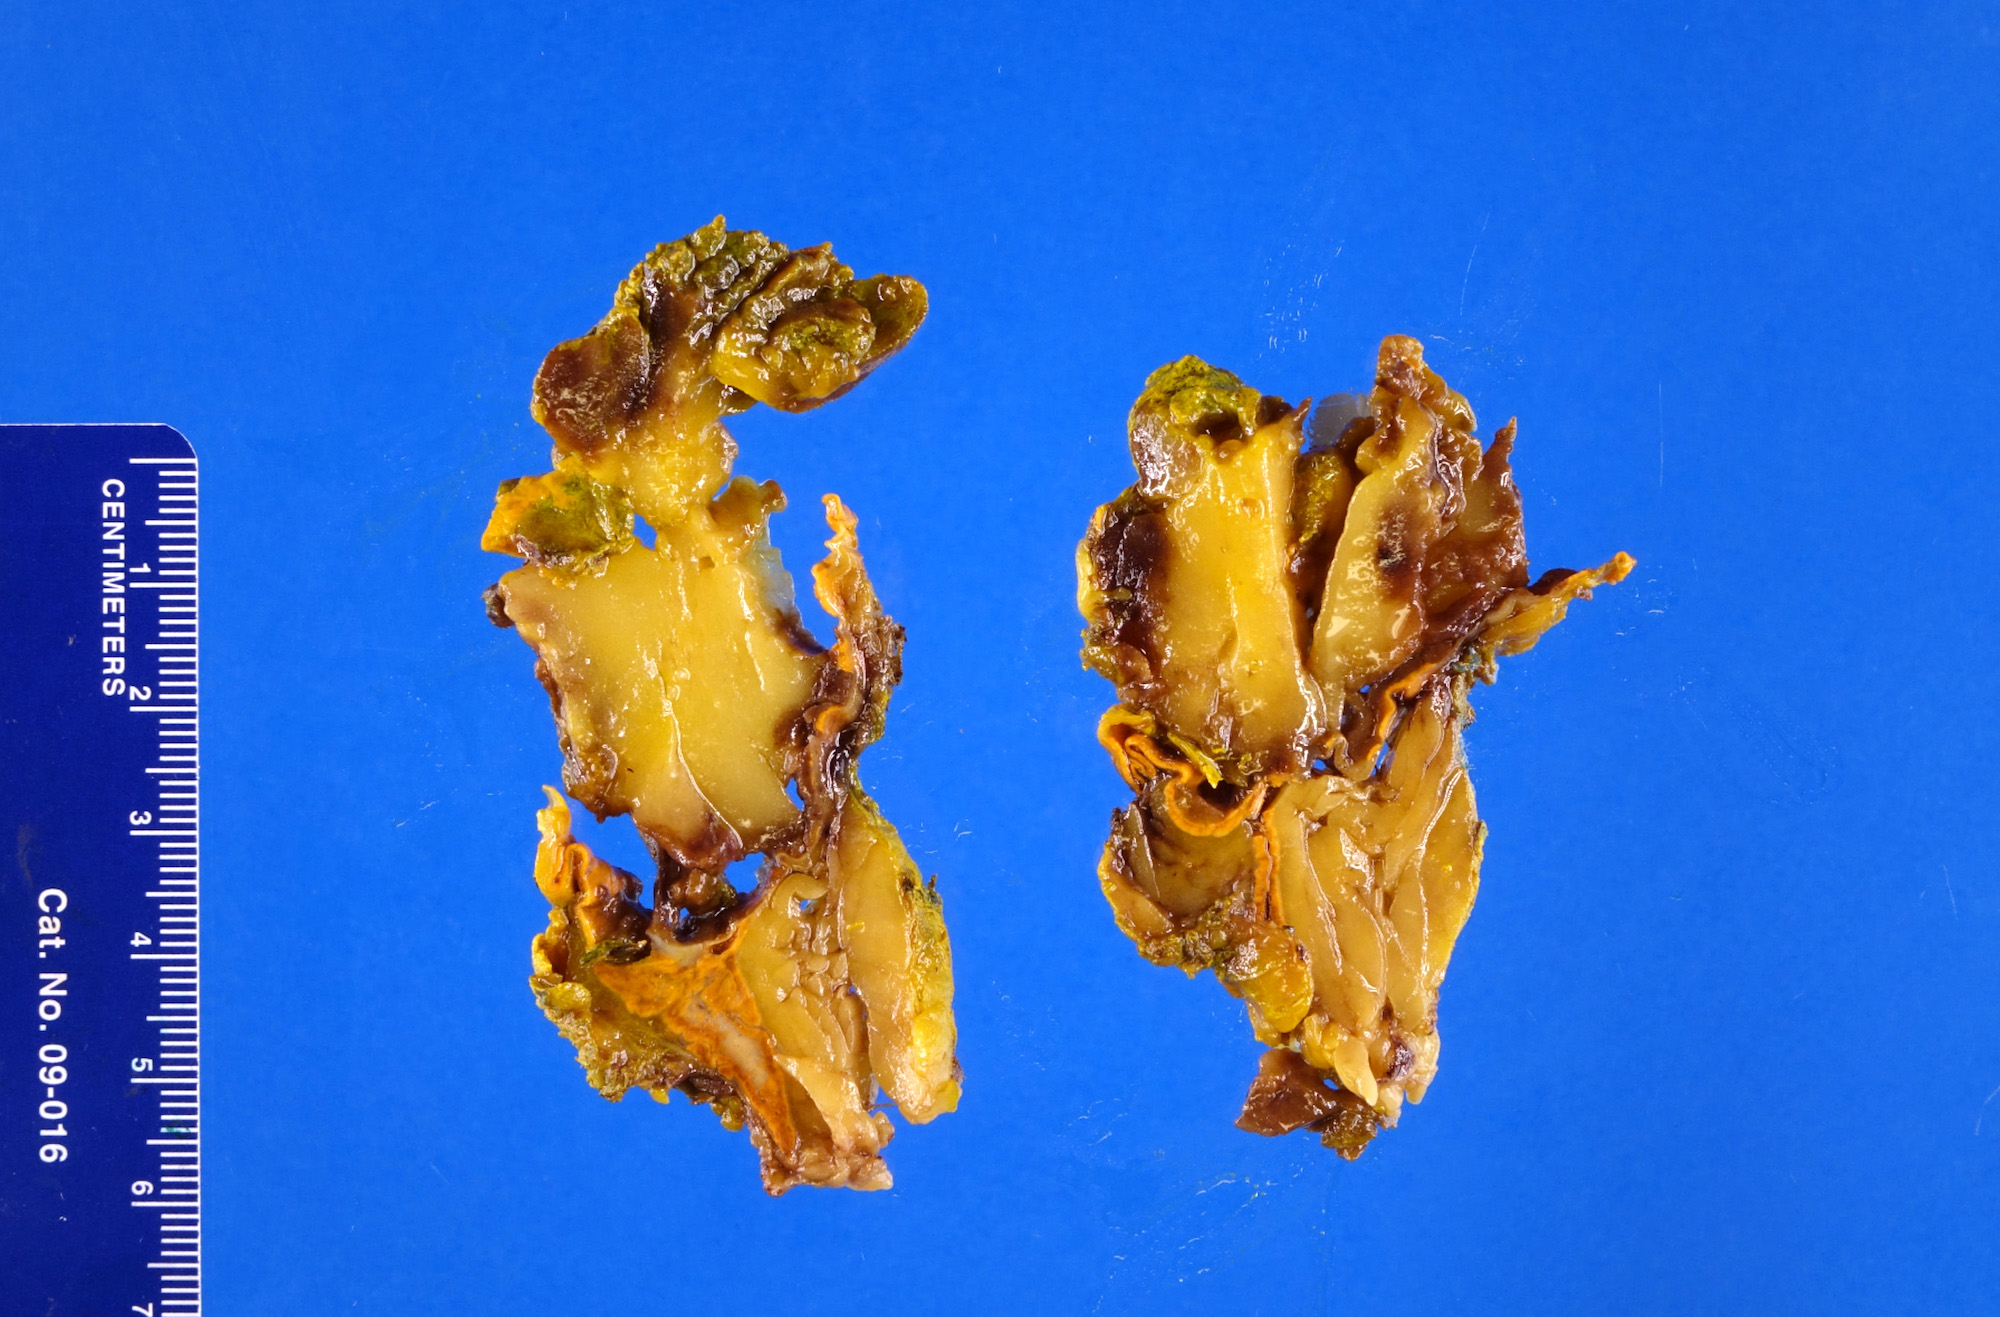

Gross description

- Well demarcated, unencapsulated, yellow (mature fat) to red (hemorrhage) nodule depending on the composition; if large, hemorrhage and infarction are common

- Mean size is 10 cm (0.5 - 43 cm); weight may be up to 11 kg

Gross images

Contributed by Debra L. Zynger, M.D. and Anil Parwani, M.D., Ph.D.